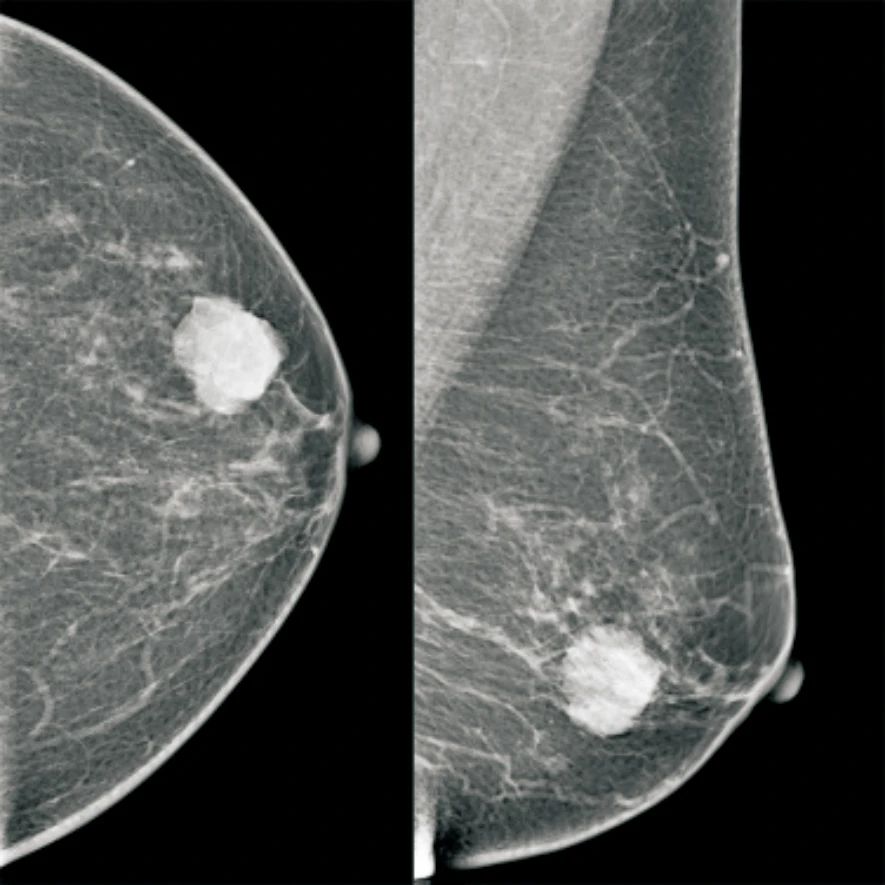

在所有影像学特征中,肿块边缘和钙化分布的差异有统计学意义(P<0.001和P=0.005)。区域性钙化分布(图1)平均RS为39.9,明显高于段样钙化(24.4)和集群样钙化(31.8)(P<0.001,图2)。边缘清楚肿块(图3)的患者平均RS为17.4,明显低于肿块边缘表现为毛刺(27.4)、遮蔽(25.3)和模糊(28.5)的患者(图4)。

图 1 乳腺X线摄影区域分布钙化

Fig. 1 Regional calcifications on mammogram

Images in a 40-year-old woman whose breast tissue was heterogeneously dense. Mammogram showed regional fine pleomorphic calcifications in left breast. Postoperative pathology confirmed invasive ductal carcinoma and DCIS(RS=40.7)

图 3 乳腺X线摄影边缘清楚肿块

Fig. 3 A mass with circumscribed margin on mammogram

Images in a 53-year-old woman whose breast tissue was almost entirely fatty. Mammogram showed a 27 mm×25 mm mass with circumscribed margins in lower outer left breast. Postoperative pathology confirmed pure mucinous breast cancer(RS=35.7)